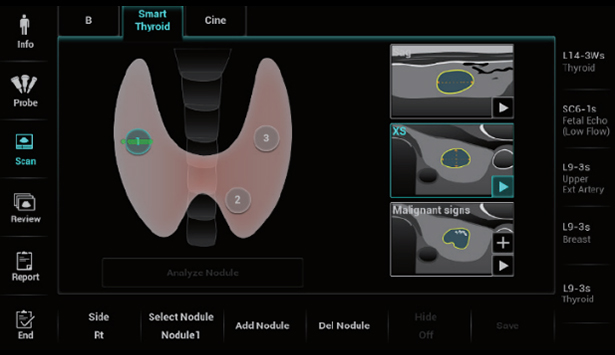

КУУЗИ: перфузия аденомы щитовидной железы